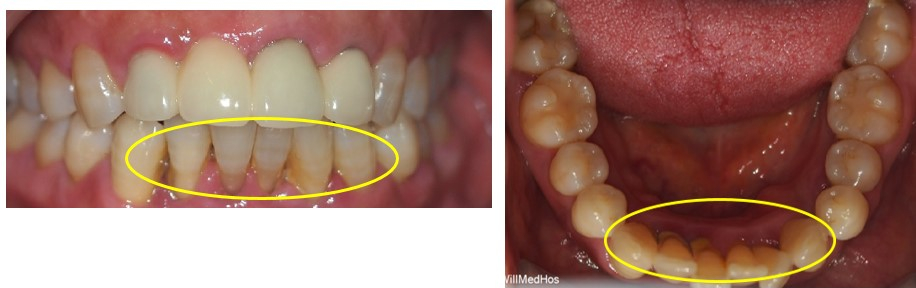

오늘은 잇몸 패임으로 앞 쪽 아랫니 통증과 함께 치아의 흔들림이 전보다 많이 느껴져 내원해주신 환자분입니다.

먼저 처음 구강 사진 부터 보도록 하겠습니다.

▲ 초진 구강 사진

환자분은 표시된 부분의 치아의 통증을 느끼셔서 내원 하셨습니다

잇몸이 패여 '치주염' 으로 인해 잇몸이 다 녹아내려 '치경부 마모증'까지도 같이 있으신것을

확인 할 수 있었습니다.